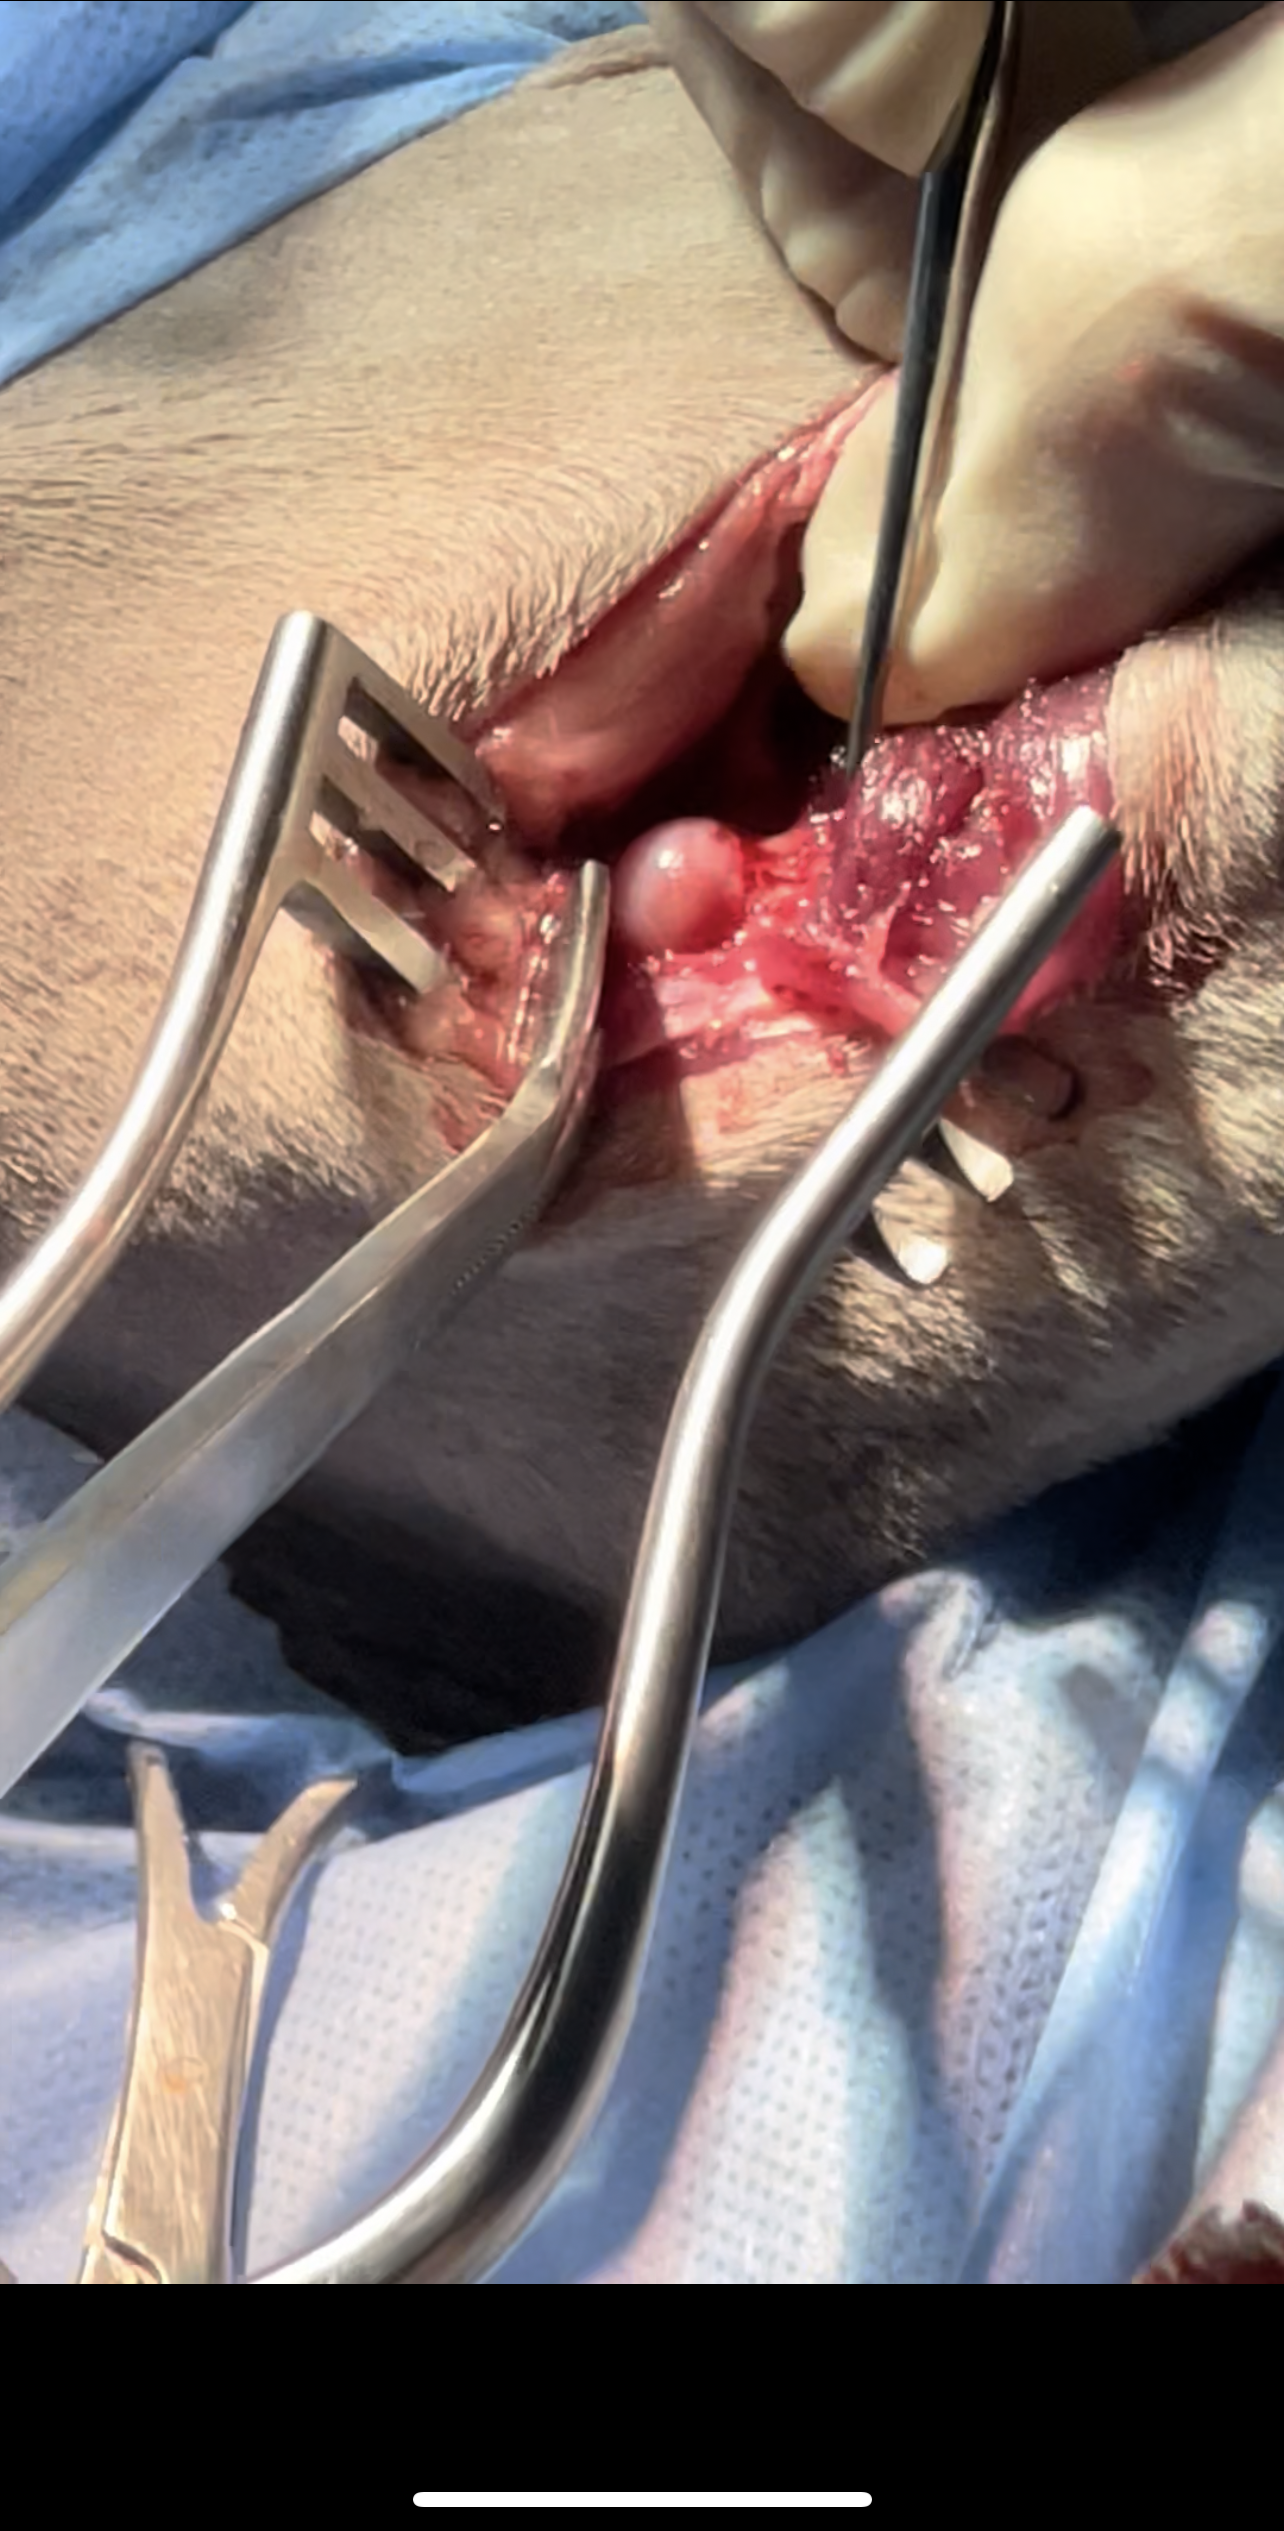

The surgery involves removing the femoral head and neck, thereby eliminating bone-to-bone contact and allowing a fibrous pseudoarthrosis (“false joint”) to form

Surgery

Bilateral FHO was recommended starting with the right most affected limb and the other to be scheduled after 2 months